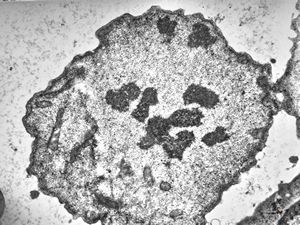

M,62y. | mitosis - plasmocytoma